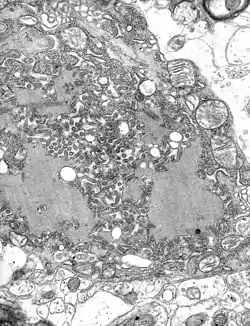

Negri bodies are eosinophilic, sharply outlined, pathognomonic inclusion bodies (2–10 μm in diameter) found in the cytoplasm of certain nerve cells containing the virus of rabies, especially in pyramidal cells[1] within Ammon's horn of the hippocampus. They are also often found in the Purkinje cells[1] of the cerebellar cortex from postmortem brain samples of rabies victims. They consist of ribonuclear proteins produced by the virus.[2]